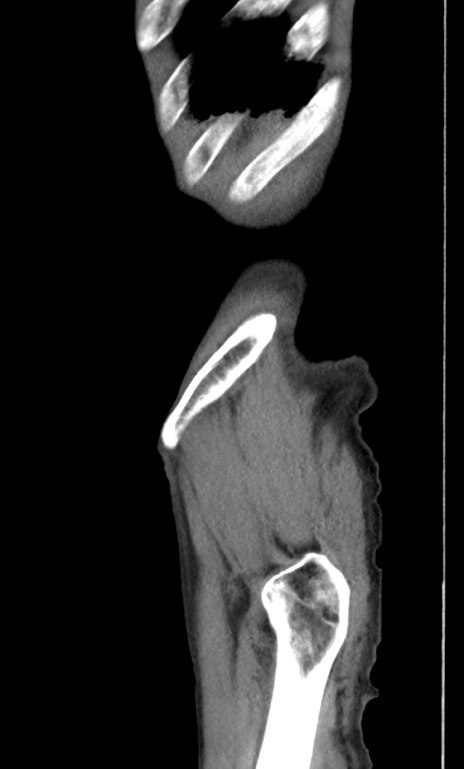

症例3(矢状断像)

症例

【症例】 70歳代男性

【主訴】右鼠径部腫瘤、疼痛

【現病歴】本日朝より上記主訴あり、受診。

【既往歴】膀胱癌にて膀胱全摘、両側尿管皮膚瘻

【データ】WBC 5600、CRP 0.56